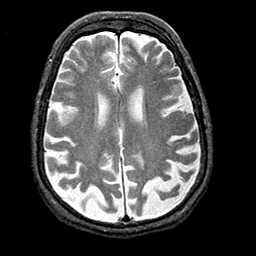

Alzheimer's disease MR T2-weighted -- Slice #31

[Home][Help][Clinical][Tour 1][Tour 2] Slice 31